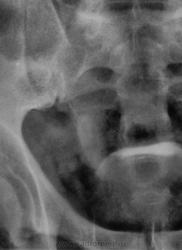

Признавайтесь, куда делась средняя треть правого мочеточника? Ее как-будто ножом отрезали под линейку, а ниже-сплошное безобразие! "ЧТО" может как обезобразить орган-банальная МКБ с частичной обтурацией просвета или опухоль? А в пузыре тоже камни?

Фи, доктор, это не латынь? Хотя можно выразиться и покрепче. Но в/в не дала ответов-где и что это?

А деформация мочевого пузыря никого не смущает?

Отчего же не смущает?))) смущает...она и есть первопричиной образования ТАКОГО камня в мочеточнике, теперь об этом можно сказать с уверенностью, ее генез - выраженое увеличение размеров простаты.

Мне кажется, что тень в проекции н/3 правого мочеточника не меняет своей интенсивности на ОМПС и экскреторных урограммах. Отсроченный снимок просится и рентгенография малого таза в косых проекциях. Возможно, это НЕЧТО сдавливает н/3 правого мочеточника извне.

С простатой при отсутствии УЗИ достаточно пальцевого осмотра хирургом до экскреторного исследования. Если простата не увеличена пальпаторно, то получив такую картинку мочевого пузыря на первых минутах после введения контраста, я бы сделал косые снимки мочевого пузыря (заодно и тень в н/3 правого мочеточника покрутить).